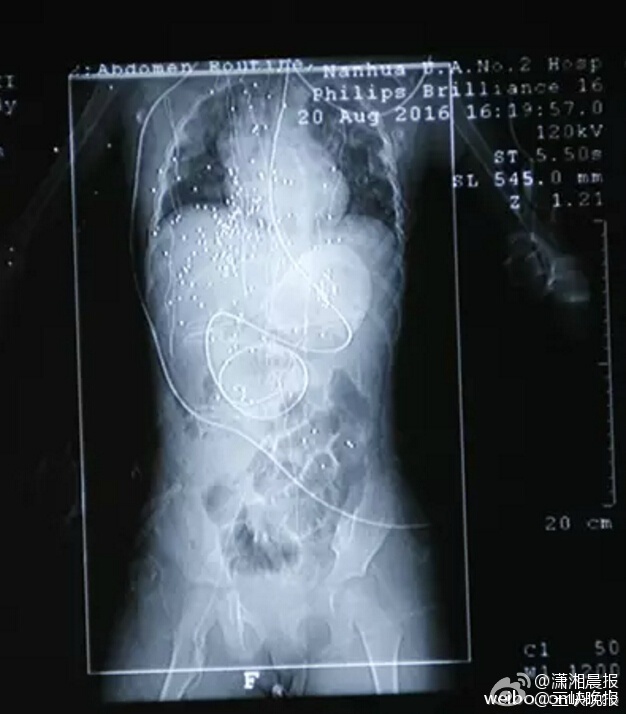

●(圖/瀟湘晚報微博)

▼目前還有百餘顆鋼珠在女童的體內。

緊急將女童送醫後,醫生進行了長達4個小時的緊急手術後,僅從她小小的身體中取出20多顆鋼珠,還有幾百顆的鋼珠在她的體內,還會隨著血液流動,醫院需要為她進行抗感染的治療,預防併發症及破傷風。醫生表示,由於鋼珠體積比較小,大約只有黃豆的大小,若貿然再進行手術,可能會對女童造成更大傷害,所以在不影響內臟的前提下,先讓鋼珠在體內「共存」。